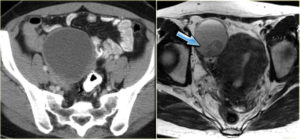

МРТ малого таза. Стрелкой указан яичник и геморрагический компонент в нем

МРТ малого таза. Гиперинтенсивные очаги свидетельствуют о жидкости в маточных трубах у женщины

МРТ малого таза. Серозная киста правого яичника

МРТ малого таза. У пациентки нарушение менструации и выраженная правосторонняя тазовая боль. Стрелкой указано патологическое образование.

Муцинозная цистаденома. Гипоинтенсивный сигнал на Т1 и гиперинтенсивный сигнал на Т2.